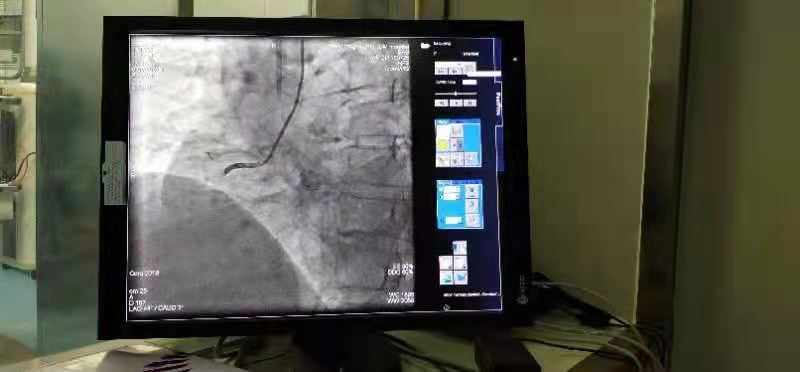

1月14日下午,在鄲城縣第二醫(yī)療健康服務集團鄲城縣中醫(yī)院心病一區(qū)手術(shù)室,經(jīng)過充分的術(shù)前準備,集團總醫(yī)院副院長、心病一區(qū)主任楊俊帶領團隊,為44歲的冠心病患者朱某男成功實施了心臟冠脈支架介入治療。與以往手術(shù)不同的是,患者朱某男享受到了國家集采政策后降價的冠脈支架,其植入的冠脈支架從原先每枚均價數(shù)萬元降為700元。

手術(shù)的順利完成,也標志著首批國家集中采購的醫(yī)用耗材冠脈支架在我院正式落地實施。